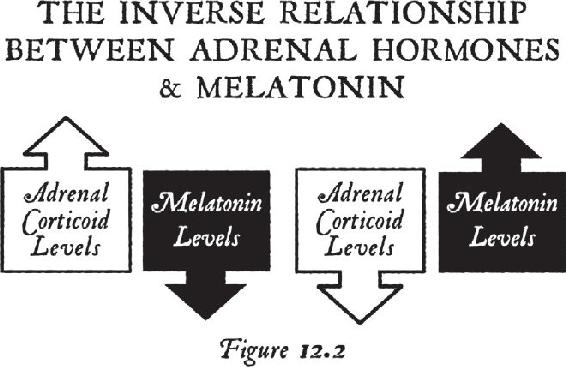

Once you are beyond your associations to this material world and you are in the unified field—chock-full of infinite possibilities—biological systems exist for taking that energy that’s beyond the vibration of matter and turning it into imagery in the brain. That’s where the pineal gland comes in, the subject of Chapter 12. Think of your pineal gland—a tiny gland perched in the central back area of your brain—as an antenna that can transduce frequencies and information and turn them into vivid imagery. When you activate your pineal gland, you are going to have a full-on sensory experience without your senses. That internal event will be more real to you in your mind while your eyes were closed than any past external experience you’ve ever had. In other words, in order to lose yourself fully in the inward experience, it has to be so real that you are there. When this happens, this little gland transmutes melatonin into some very powerful metabolites that cause you to have that type of experience. We will study the properties of this gland and then you will learn how to activate it.